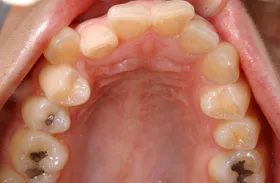

金属を白くし、歯茎の黒ズミを改善したケース

■治療前

■治療後

| 主訴 | 全体的に白い歯にして見た目をきれいにしたい 歯茎が黒くなっているのが気になる、歯ならびも良くしたい |

|---|---|

| 治療方法 | 矯正治療+歯茎の黒ずみの改善+補綴治療 |

| 治療期間 | 3年 |

| 通院回数等 | 約40回 |

| 費用 | 約350万円 |

| リスク・副作用 | 矯正治療も行ったので治療期間が長くなった |